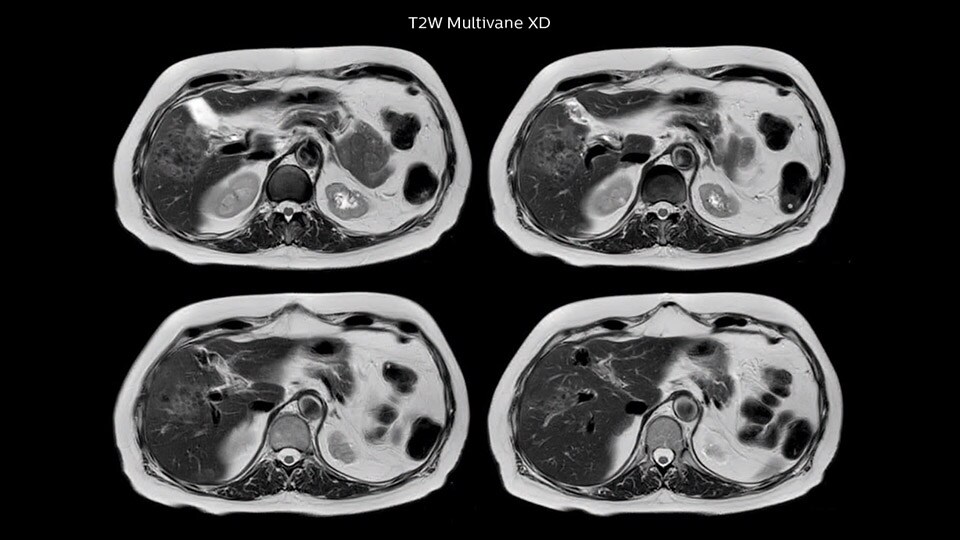

Ultimate precision at maximum speed with Dual AI

Take the leap forward with SmartSpeed Precise, the next generation acceleration technique that expands the proven Compressed SENSE and SmartSpeed technologies with a unique integrated Dual AI innovation, providing ultimate precision at maxiumum speed.

Read more

SmartSpeed Precise